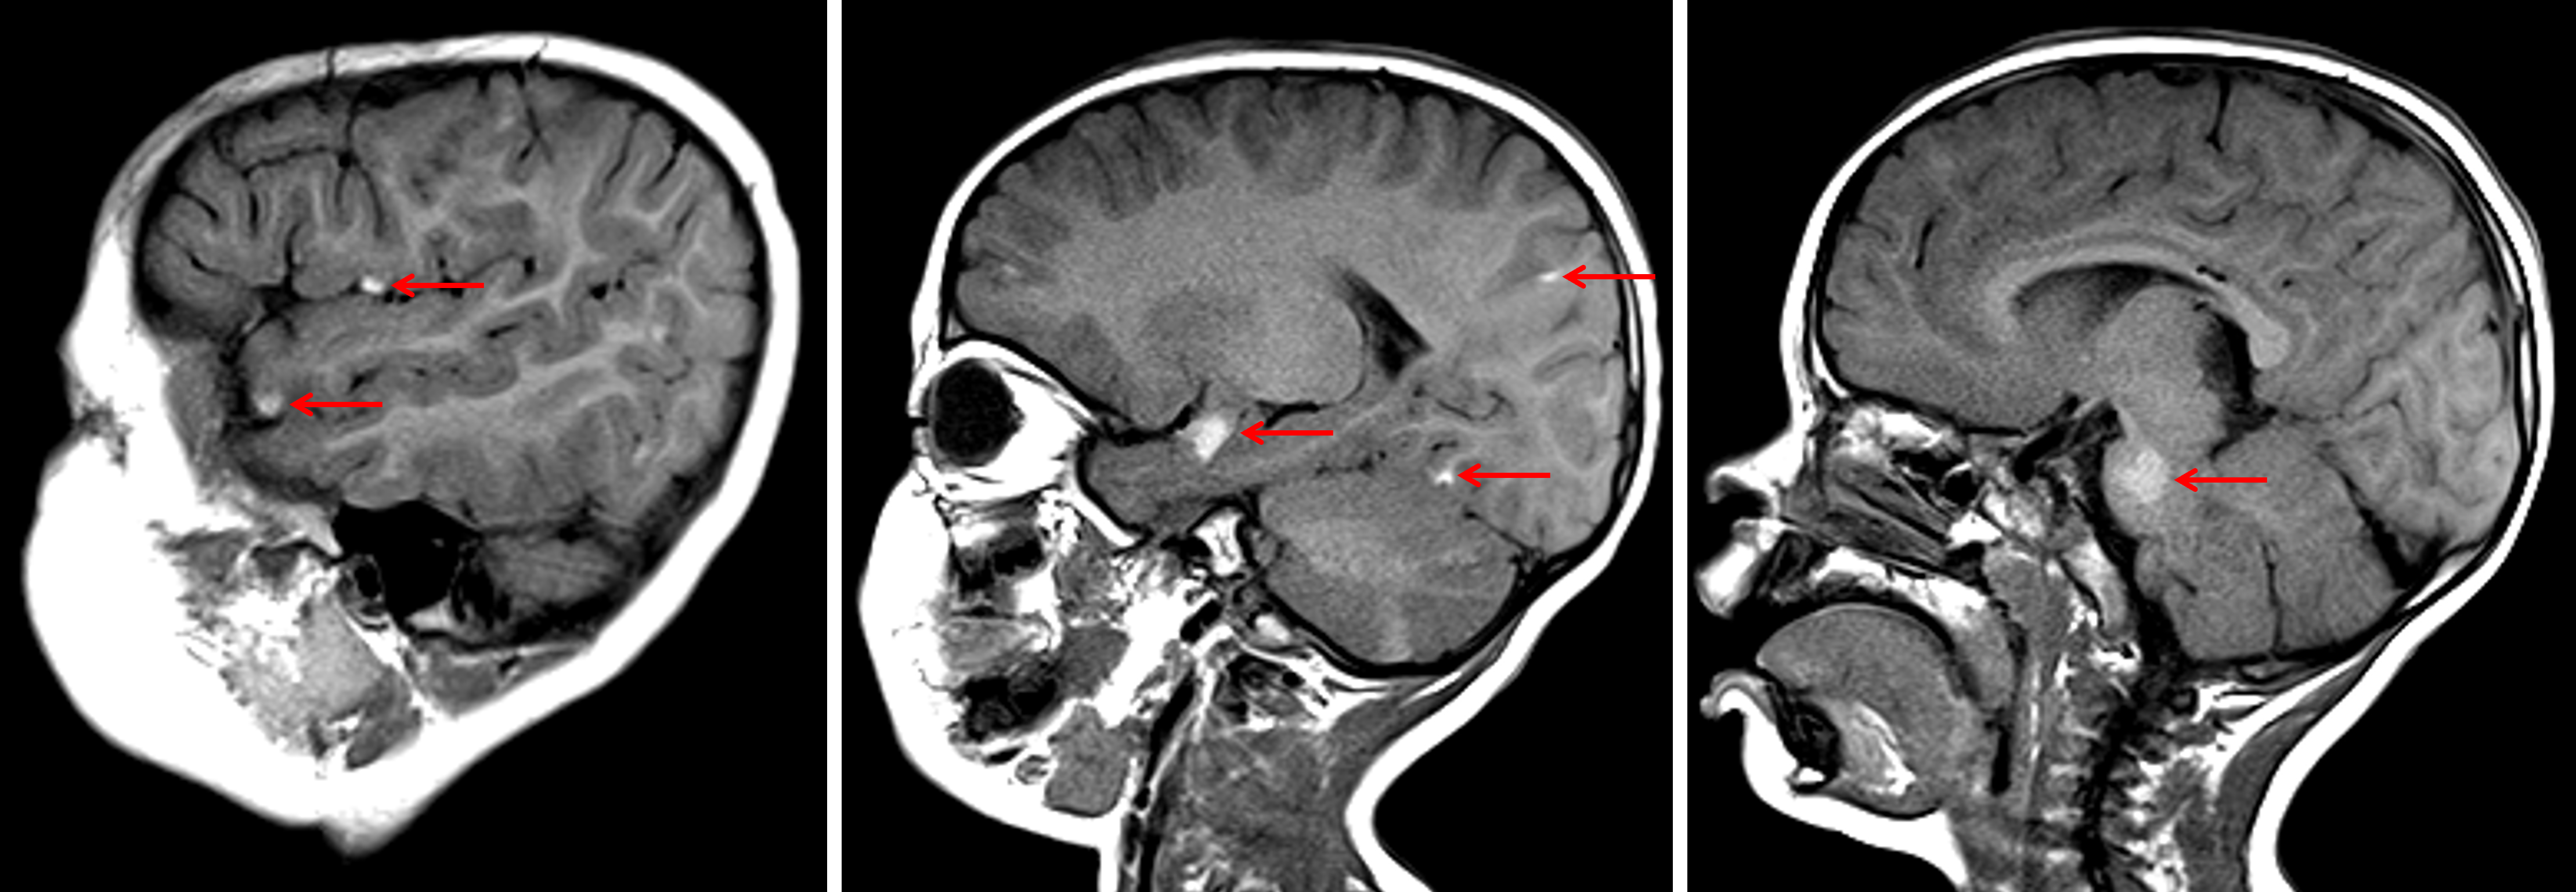

Age: 2

Sex: Female

Indication: Imbalance, large nevus on back

Meningeal melanocytosis (neurocutaneous melanosis)